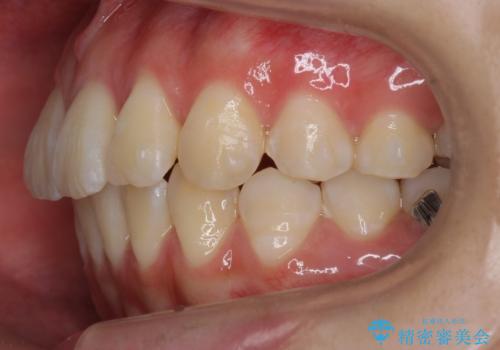

出っ歯 軽度のがたつき インビザラインで

- 奥歯を後ろに下げる処置をおこなっています。

前歯にオープンバイト気味の症状がありましたが、前歯を後ろに下げることでしっかりかませています。

前歯のずれも治り、しっかり下がりました。

前歯を下げるのに、顎間ゴムを使用していただいています。